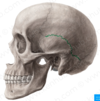

Juvenile/ Adult Skull Flashcards

(49 cards)